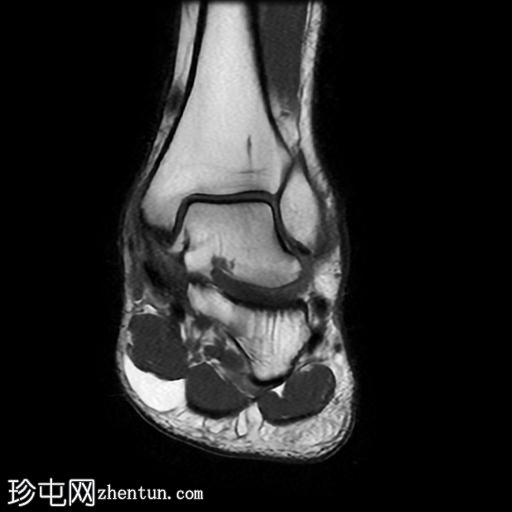

冠状位

T1加权像

冠状位PD脂肪抑制序列

跟骨前突延长增宽,与舟骨形成不规则关节,形似“食蚁兽

鼻

”。

该异常跟舟关节处可见关节下骨髓水肿。此外,舟骨内外侧径增宽,向外侧逐渐变细,并与增大的跟骨前突形成关节。

距舟关节轻度积液,并可见边缘骨赘。